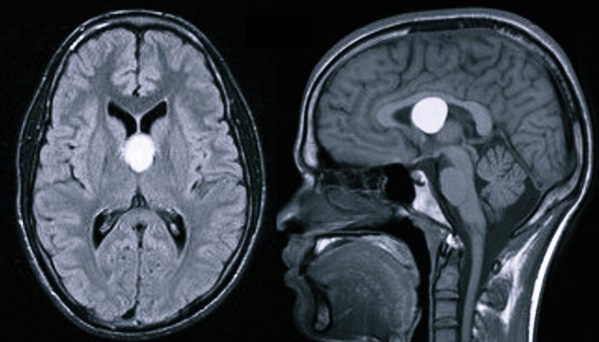

Киста шишковидной железы (пинеальная киста) — кистозное образование эпифиза. Отдельные данные свидетельствуют о том, что до 10 % людей имеют малые бессимптомные пинеальные кисты. Кисты диаметром более 1 см отмечаются намного реже и могут давать клиническую симптоматику. При достижении значительных размеров, киста шишковидной железы способна перекрывать вход в водопровод мозга и блокировать ликвороциркуляцию, обуславливая окклюзионную гидроцефалию.

image

Использование УЗИ позволяет выявить некоторые врожденные кисты еще в период внутриутробного развития, после рождения ребенка и до закрытия его большого родничка диагностика возможна при помощи нейросонографии. В дальнейшем визуализировать кисту можно посредством КТ или МРТ головного мозга. Для дифференцировки кистозного образования от опухоли мозга эти исследования проводят с контрастированием, поскольку в отличие от опухоли, киста не накапливает в себе контрастное вещество. Для лучшей визуализации кистозной полости возможно введение в нее контраста путем пункции кисты. В отличие от МРТ, КТ головного мозга дает возможность судить о вязкости содержимого кисты по плотности ее изображения, что учитывается при планировании хирургического лечения. Основополагающее значение имеет не только установление диагноза, но и непрерывное наблюдение за кистозным образованием для оценки изменения его объема в динамике. При постинсультном генезе кисты дополнительно прибегают к сосудистым обследованиям: дуплексному сканированию, УЗДГ, КТ или МРТ сосудов головного мозга.